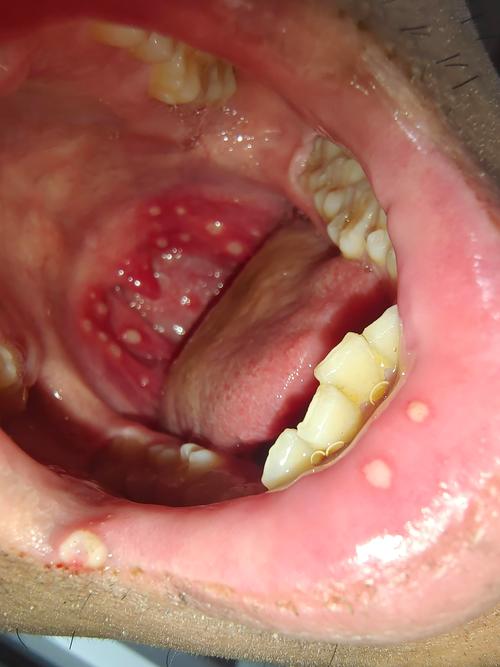

口腔溃疡白色假膜能强行挖掉吗?

千万不要自己用手或工具去挖掉口腔溃疡上的白色假膜!

加重疼痛和刺激:白色的假膜(医学上称为“纤维蛋白膜”)是溃疡表面的一层保护膜,它虽然看起来像“坏掉”的组织,但实际上是身体修复过程中形成的天然“创可贴”,强行挖掉会暴露下方娇嫩、暴露的溃疡面,就像撕开正在愈合的伤口一样,会立刻引起剧烈的疼痛,并刺激溃疡扩大。